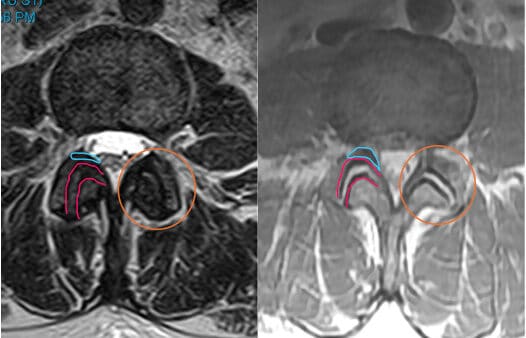

MRI of the spine without (left) and with (right) age-related changes in the joint (orange circle). The red outline is the space between the joints. Notice how on the left image, there is less white and less space between the two lines, while on the right, there is more white and more space. This is evidence of increased joint fluid and inflammation. The blue line on each image highlights the yellow ligament, which gets thicker with joint inflammation and stress. These changes are common as people age, but can cause pain in some patients.